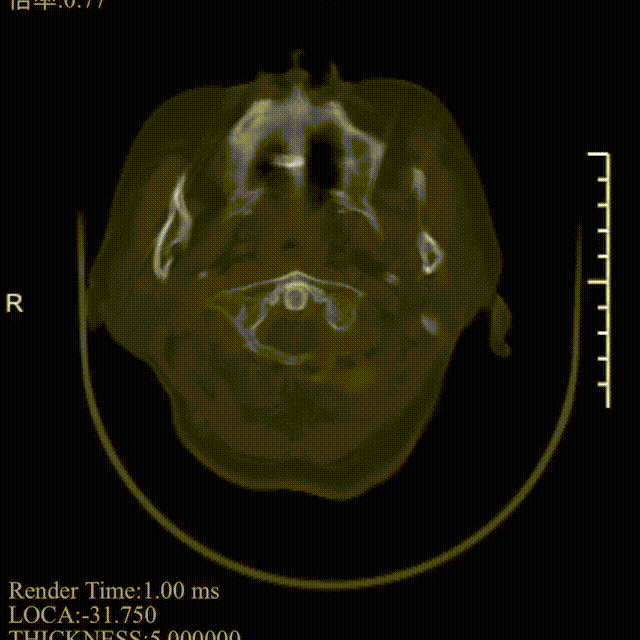

术前影像学检查

左侧丘脑及双侧侧脑室旁白质区可见点片状低密度影,影像诊断左侧丘脑及双侧侧脑室旁白质区腔隙性脑梗塞;老年性脑改变。